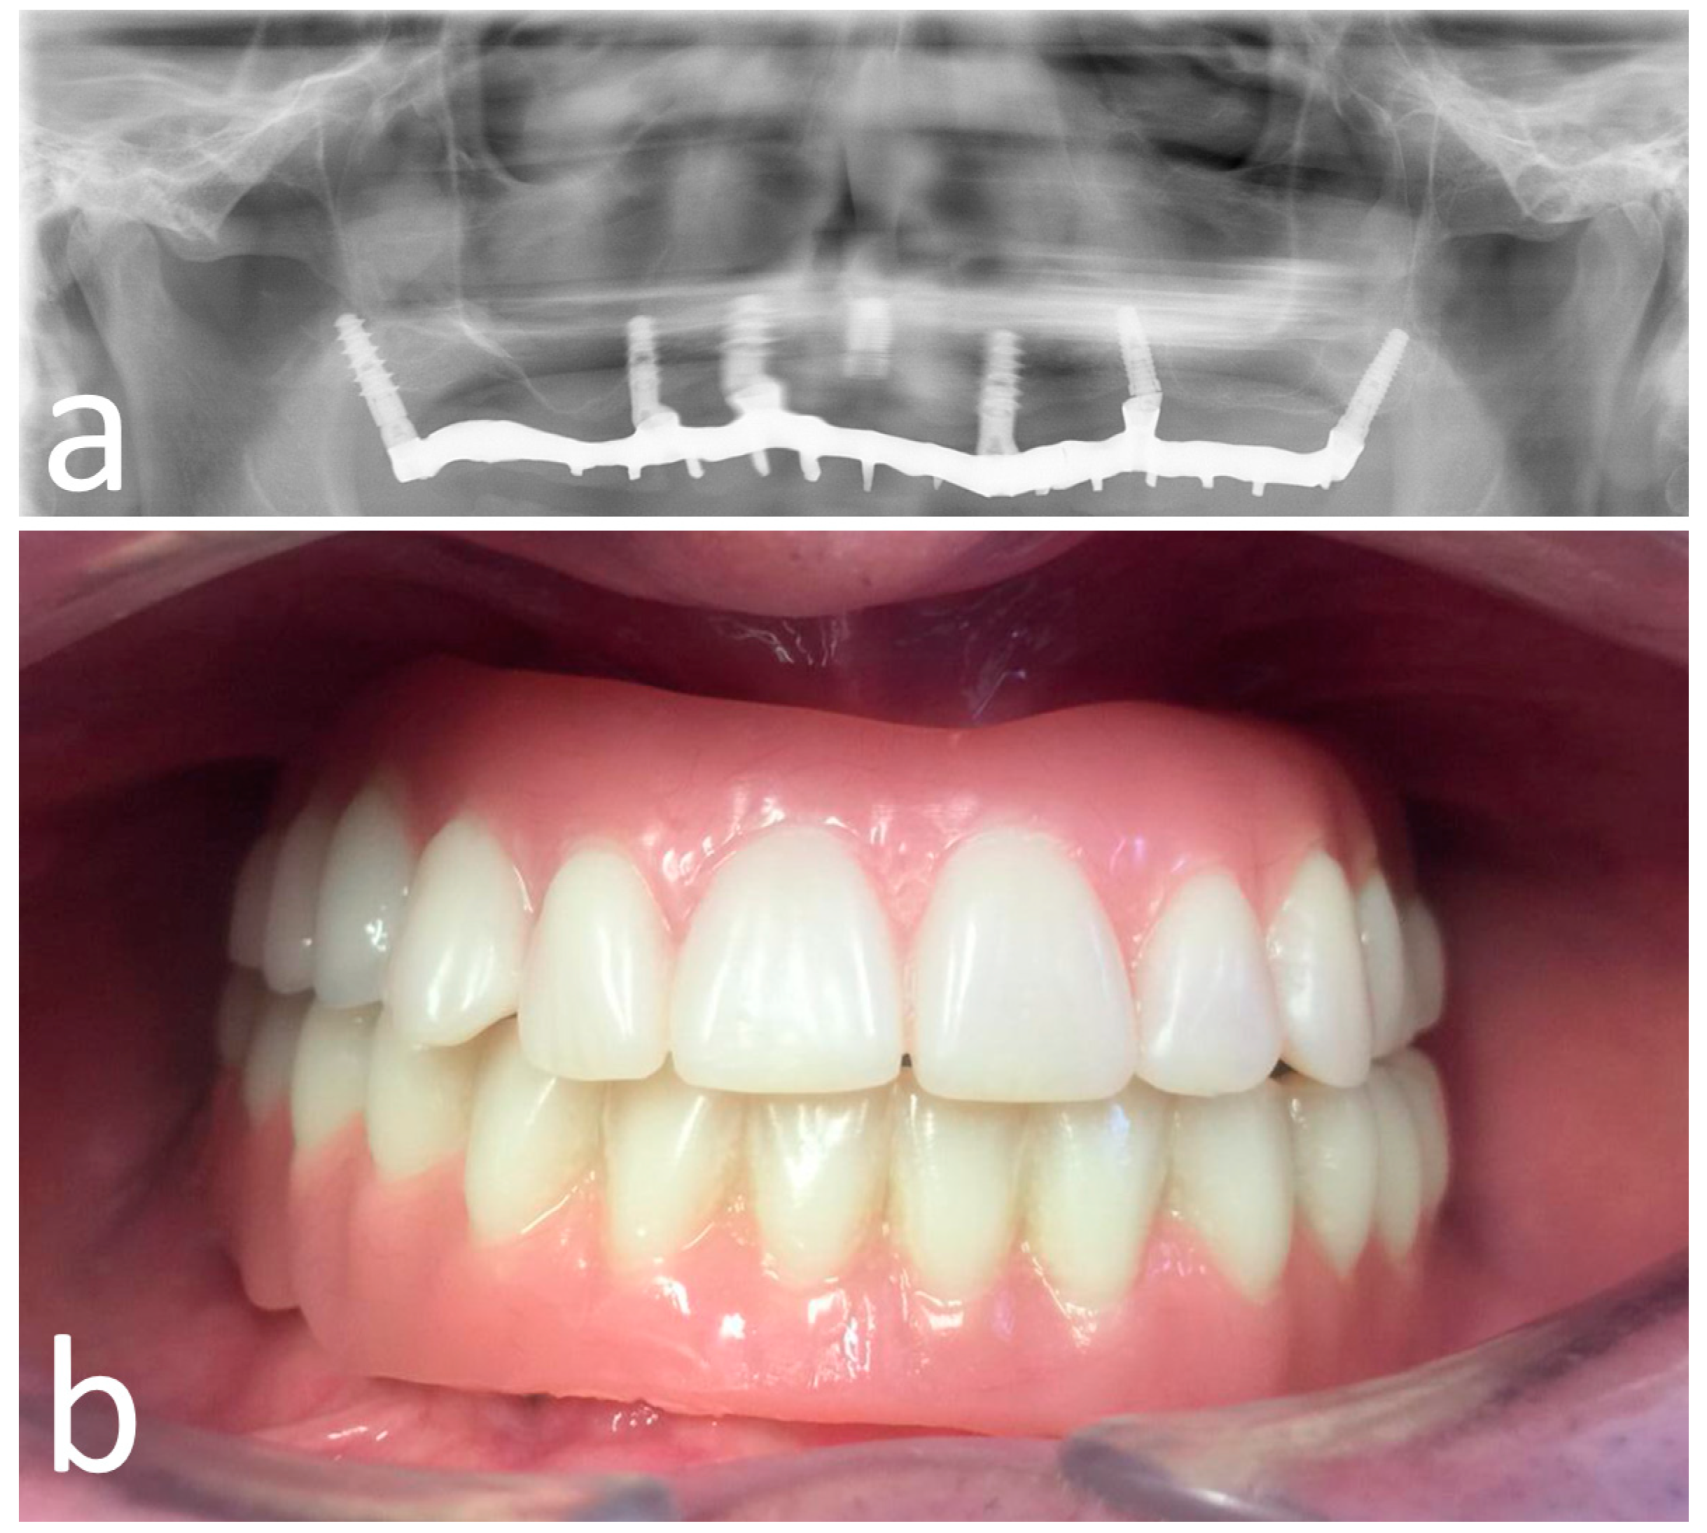

Figure 7.

Opt X-ray (a) and clinical (b) view of the provisional prosthesis realized using conventional straight and angled multi-unit abutment (M.U.A.).